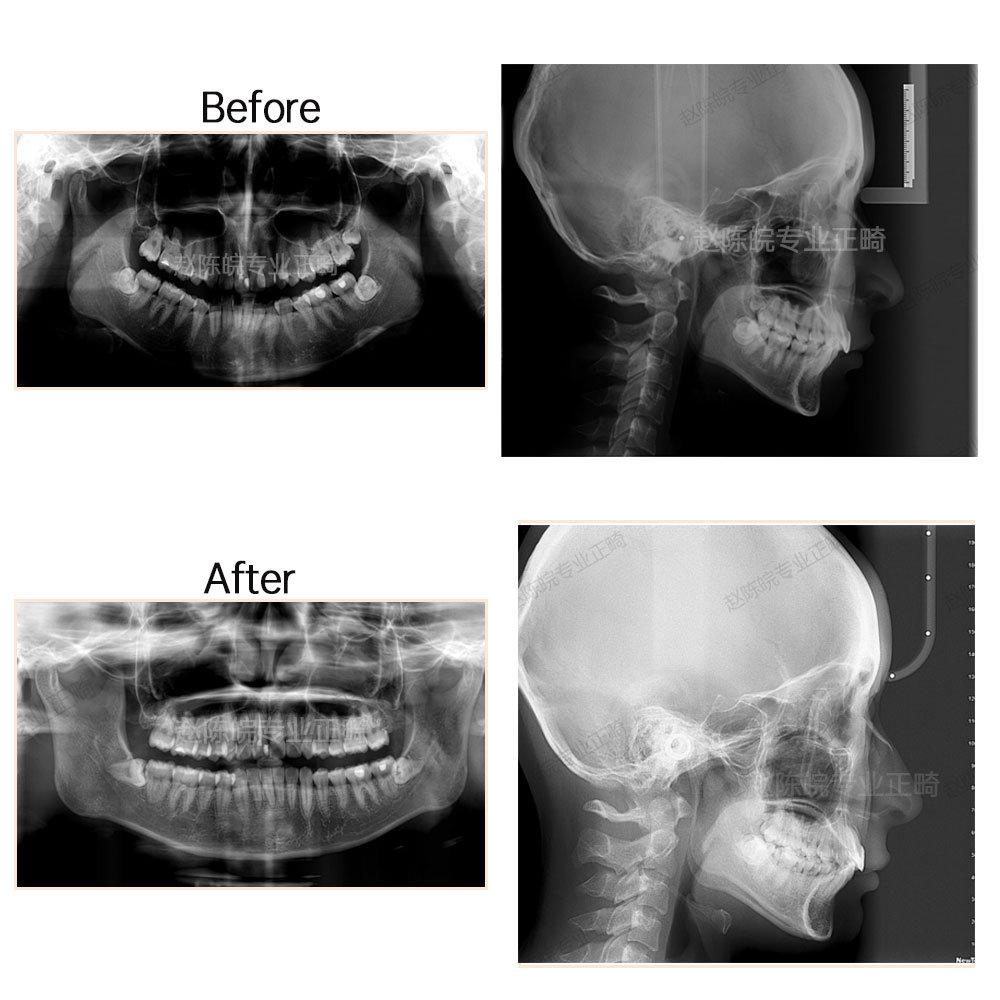

?矯正前后X線(xiàn)片前后對(duì)比圖(觀察對(duì)比側(cè)面顱骨情況及牙體牙周情況)

矯正前中后牙齒口內(nèi)對(duì)比照(觀察牙齒排列、牙弓形態(tài)、覆合覆蓋及咬合情況)